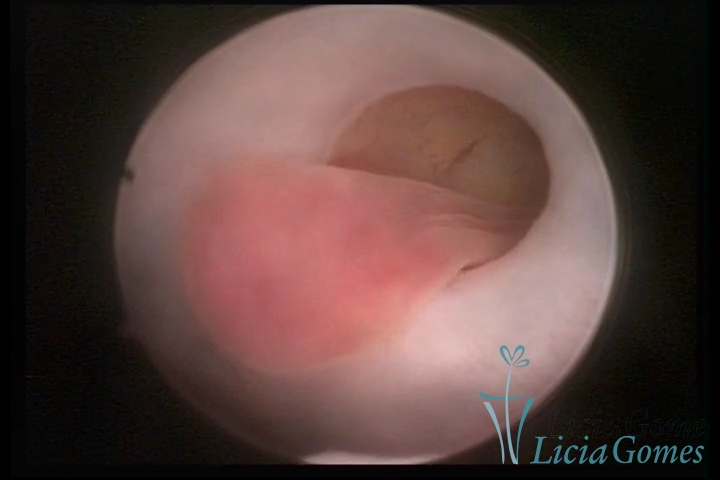

PÓLIPOS ENDOCERVICAIS

São tumores benignos, resultantes da proliferação focal reativa aos processos inflamatórios ou à situações de hiperestrogenismo, e podem ter sésseis (com a base de implantação larga) ou pediculados do epitélio.